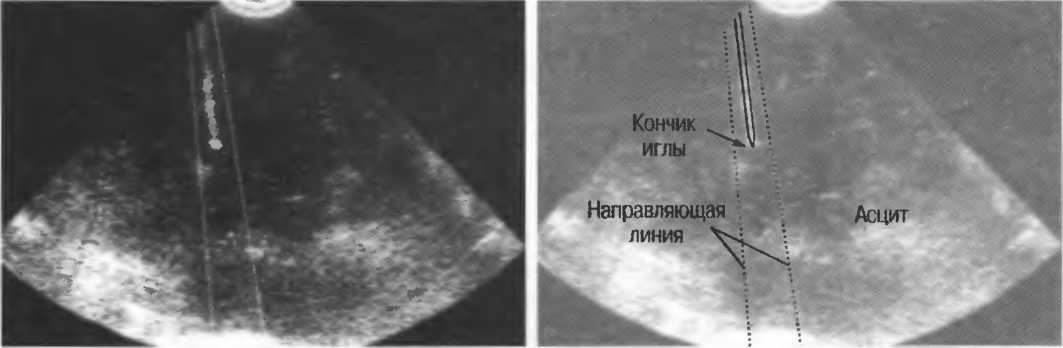

На практике, наиболее значимые в клиническом плане артефакты возникают при проведении биопсии или аспирации под контролем ультразвука. До тех пор пока кончик иглы не появится в плоскости сканирования на экране, он не будет визуализироваться, и может создаться ложное представление о том, что игла значительно короче (рис. 21в).

Рис.21 в. Изображение иглы в емкости с водой. Слева игла находится в плоскости сканирования не полностью, в результате чего выглядит короче, чем есть на самом деле (крестик определяет реальную глубину проникновения иглы). Справа игла визуализируется полностью.